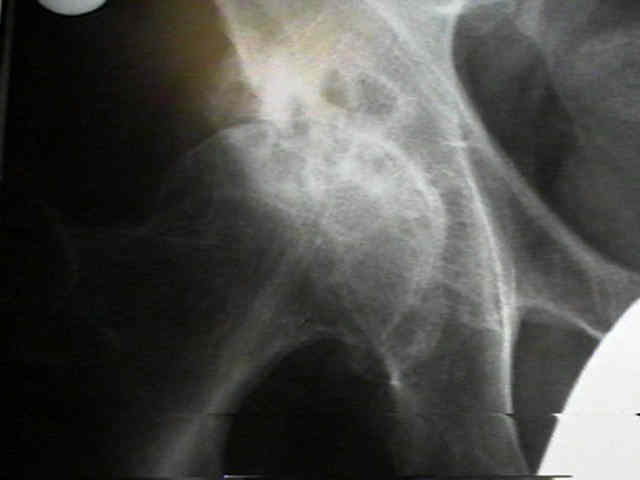

Hip Osteoarthritis

Hip Osteoarthritis 2

• pain on wt-bearing felt in the groin, buttock, or medial thigh;

• trendelenburg gait will decrease mechanical stress on joint and thereby lessen pain (see forces acting on hip joint);

• pain during sleep results from loss of protective function of muscular splinting;

• in some cases, a patient w/ OA of the hip will experience acute hip pain which often correlates w/rupture of subcondral cyst into the joint;